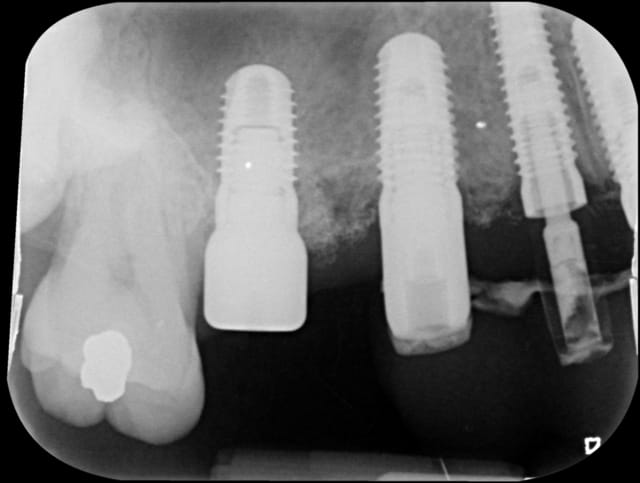

Bonjour à tous, connaissez vous ce type d'implants ?

L'environnement peri-implantaire, radiologiquement, ne semble pas des meilleurs !

L'implant le plus distal ne semble pas osseointégré.

Quand est-il cliniquement, puisqu'il semblerait à te lire que tu as récupéré le patient et ses implants et que tu t'apprêtes à faire la reconstruction prothétique supra-implantaire ?